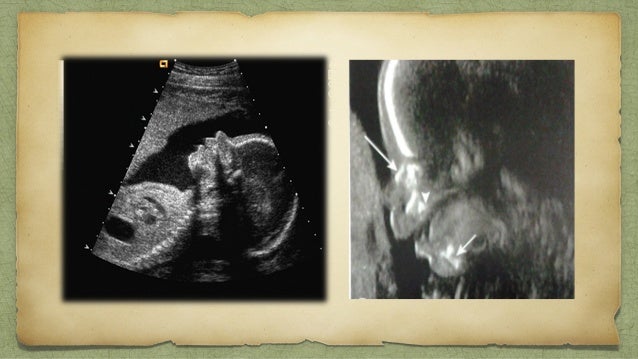

Business International Business. Increased thickness of the nuchal fold is a soft marker associated with multiple fetal anomalies and is measured on a routine second trimester ultrasound. The cartilage at the ends of the femur should not be included in the measurement.

The nonstress test NST is a simple noninvasive way of checking on your babys health. The nuchal fold is a normal fold of skin seen at the back of the fetal neck during the second trimester of pregnancy. This is called the.

The assignment of pregnancy age is the first task placed before the care provider and ultrasound. Figure 210 A and B. Assessed and reported on a routine 2 nd-trimester scan or when growth reassessment is required in the second or third trimester.